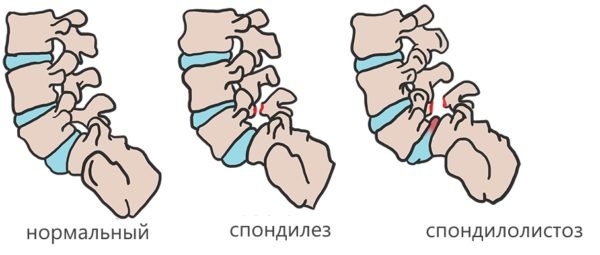

Последний пункт – это рак. К инфекциям относят туберкулез. Воспаление выражается спондилитом.

Патология[править | править код]

Механическое смещение одного из поясничных позвонков, переохлаждение, локальная инфекция, опухоли, деградация тканей, могут привести к воспалительному процессу в позвоночно-двигательном сегменте, последующим мучительным болям, вынужденным положениям тела. Очень распространённой причиной патологии в поясничном отделе позвоночника является неверное распределение нагрузки на поясничный отдел позвоночника, когда дополнительный вес (а иногда и собственный вес) поднимаются с единственным рычагом в поясничном отделе позвоночника. Частым заболеванием в поясничном отделе позвоночника являются грыжи межпозвоночных дисков — выпячивания пульпозного ядра диска за пределы его фиброзного кольца. В 48 % случаев межпозвоночные грыжи локализуются на уровне L5-S1 пояснично-крестцового отдела, в 46 % случаев — на уровне L4-L5, и лишь в оставшихся 6 % случаев — между другими позвонками поясничного, шейного или грудного отделов позвоночника.